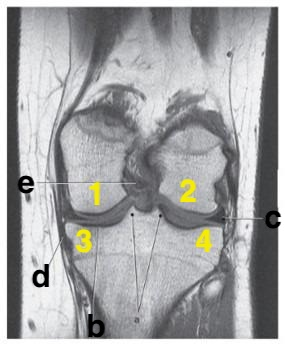

Medial meniscus

posterior cruciate ligament

What is # 4?

What imaging plane is this?

coronal

Number 2 is on the __________ side of the patient.

lateral

What anatomy is # 3?

fibula

Which letter is pointing to the patellar ligament?

b

medial collateral ligament

c

3 and 4